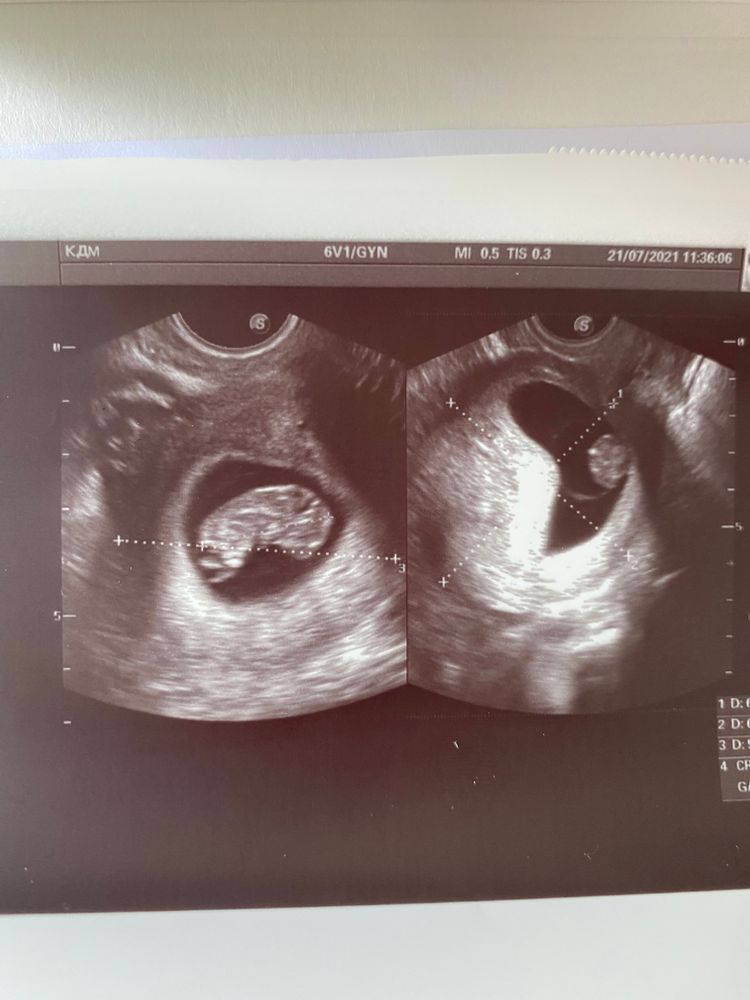

Девочки, узи сделала на сроке 8.4

ктр 23мм, а Д плодного яйца всего 27 мм

на узи в 7.4 была ктр 13 мм , плодное яйцо 31 мм

на первом фото с узи малышу уже как бы давит домик, а с другого ракурса ПЯ вытянутое